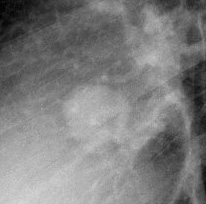

Gallery Congenital Hamartoma 1 Lat c/u

Hamartoma 1 Lat c/u